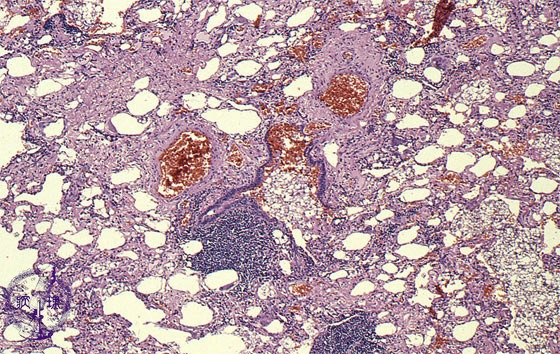

Microscopic view (HE stain, low power view): Aspirated lipoid material fills the alveoli accounting for the yellow color seen grossly and the name ggolden pneumonia.h